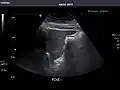

Gallbladder: No stones, wall thickening, or pericholecystic fluid.

Gallbladder

Bile duct